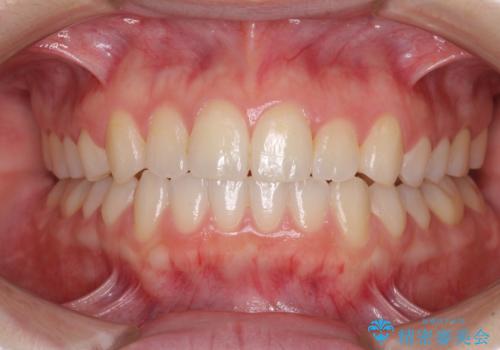

奥歯の咬み合わせを改善したいため、治療期間が長くなりましたが、患者様には辛抱強くお付き合いいただきました。

上下の正中を合わせることもでき、患者様には大変満足していただきました。